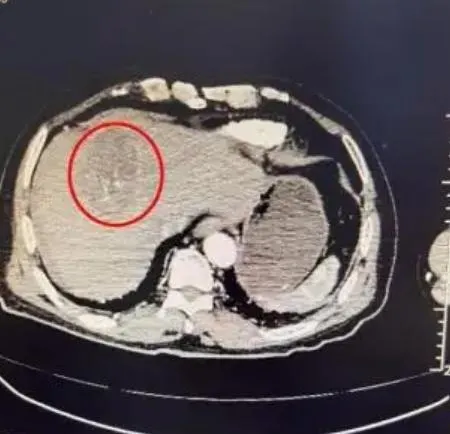

腫瘤破裂

肝癌

腹痛

腫瘤